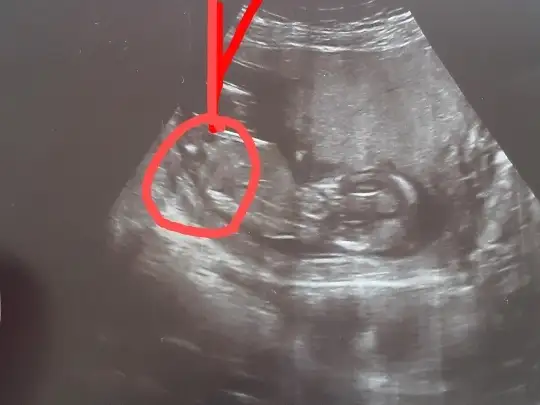

dr soylemeden siz gorun genital nub teorisi ( bebegin cinsiyeti)

Simdi 17 haftaligiz. Bu resimlerdede 12 haftaydi

Attım tekrar bundan baslada yok 12+3